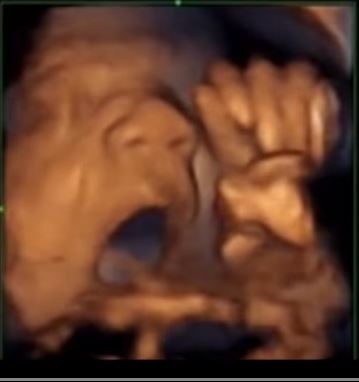

つわりもおさまってきて所謂「安定期」 と言われる妊娠16週(5カ月目)――。脳をはじめ身体の様々な器官が発達し始める時期だが、スペイン・バルセロナにある研究機関が16週目の胎児が音楽を聞くだけでなく、それに合わせるように口や舌を動かす様子を初めて確認、公開した。

胎児に音楽を聴かせている様子をエコー(超音波)で観察、記録しているが、 エコーでは胎児の45%が自然に頭や手足を動かし、30%が口や舌を動かして、そして10%が舌を出すという結果が見られたという。

特に膣内に直接スピーカーを挿入した聴かせた時には反応が顕著で、87%が頭や手足を動かす仕草を見せたそうである。これらの反応は、音楽が止まると同時にピタッと止まる様子もはっきりと見てとれたという。